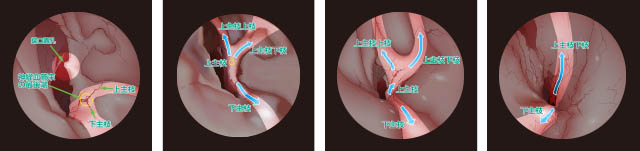

下鼻甲介の内部の構造の2Dイラスト・3Dイラスト作成のご依頼

写真をそのままトレース

説明文や部位名称をそのまま入力

ご提案後:説明に必要では無い部分をシャドウにして必要な部分を目立たせる

3Dイラスト

下鼻甲介の内部の構造の2Dイラスト・3Dイラスト作成のご依頼